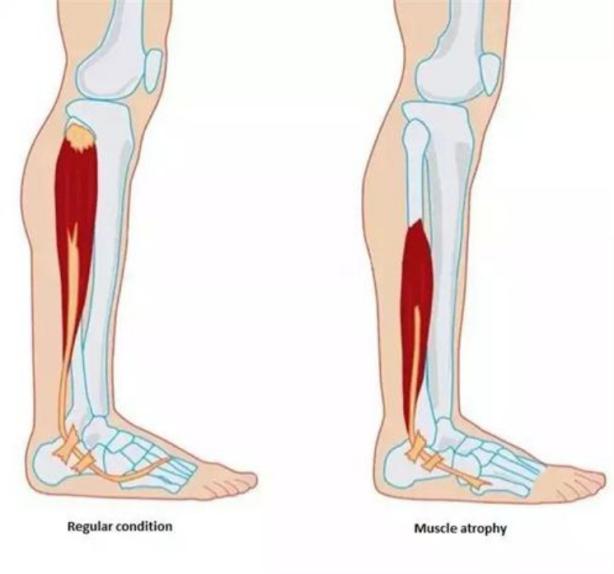

图表 2 久坐导致肌肉萎缩示意图 骨盆前倾示意图

在严格的制动中,治疗师已开始通过神经肌肉电刺激,维持肩周肌肉的活性,对抗萎缩。